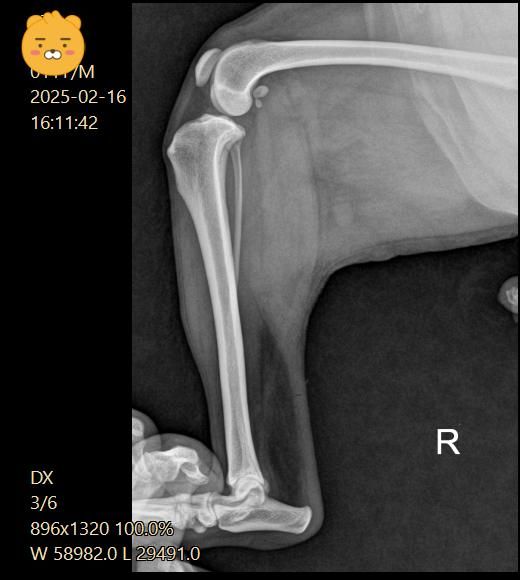

5일 간격으로 엑스레이를 찍었어요

5일후 진료는 십자인대는 애매하고 슬개골 2기로 수술 권유 받았어요

십자인대는 열어봐야 알 것 같다고 하셨고요

(두번째 진료)

우측 관절낭이 좌측에 비해 종창 되어 관찰되고 경골 경사면 각도가 비교적 크게 관찰되어 십자인대에 손상이 있을 가능성이 있는 사진입니다. 이를 확인하기 위해서는 MRI 촬영이 필요하지만 현실적인 검사 방법은 아니라 추정일 뿐입니다. 하지만 방사선학적 관점에서 십자인대의 인장성 손상은 합리적인 추론입니다.